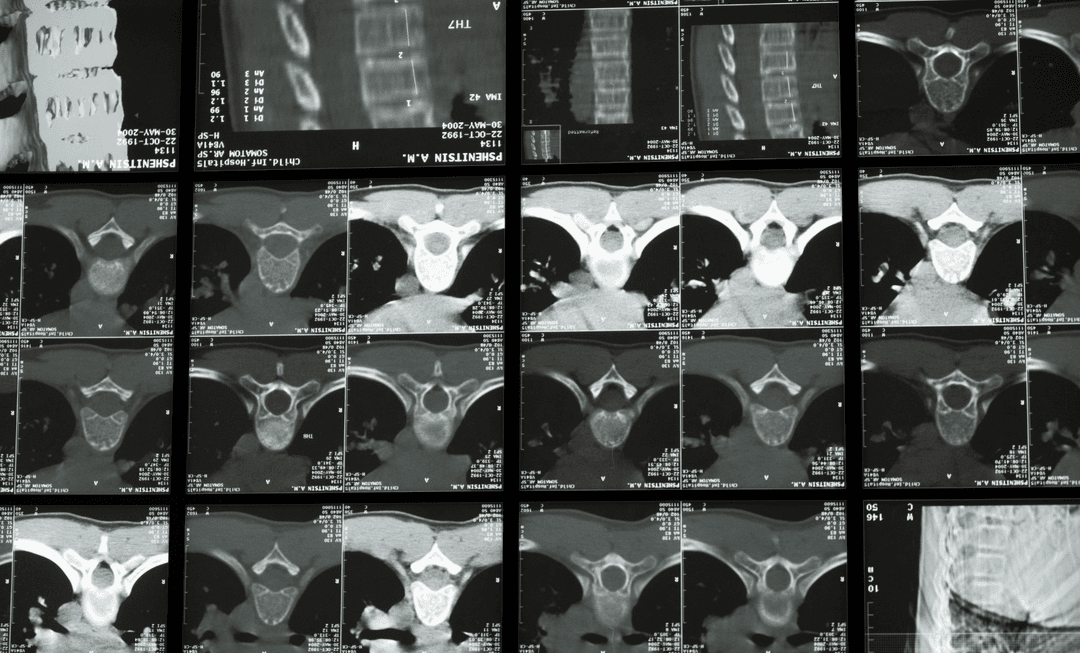

Spinal pain remains one of the most complex areas in medico-legal reporting, particularly where imaging does not align with symptom severity.